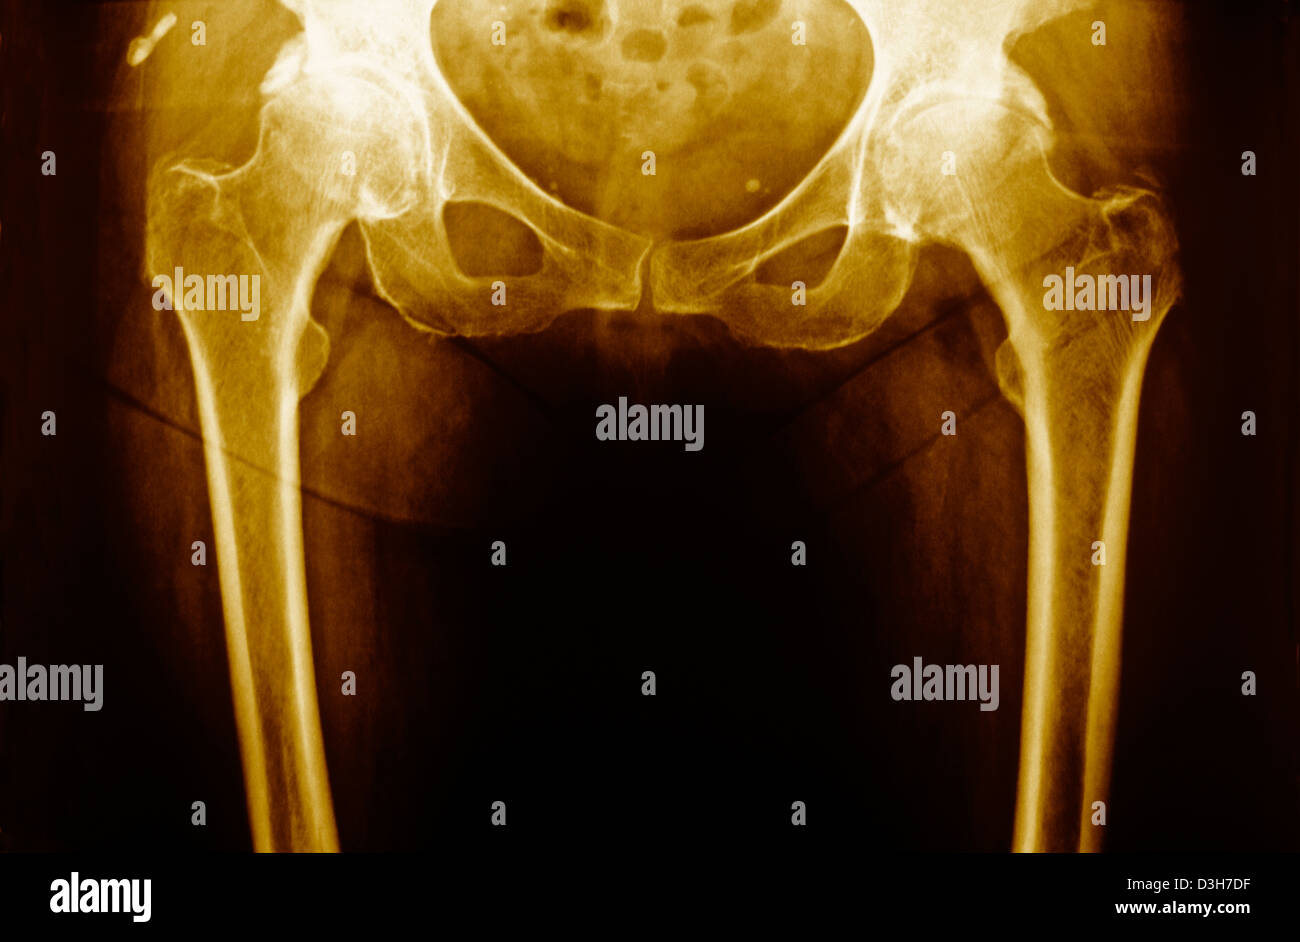

HIP OSTEOARTHRITIS, XRAY Stock Photo Alamy Hip Osteoarthritis X Ray Radiopaedia Currently, the most common radiographic. The diagnosis of oa is based on a combination of radiographic findings of joint degeneration and. Osteoarthritis (oa) is the most common disease of the hip joint seen in adults. Diagnosis can be made with. Typical osteoarthritis findings include joint space narrowing, osteophytes, subchondral sclerosis, and subchondral cysts. Different grading schemes are described for plain. Hip Osteoarthritis X Ray Radiopaedia.